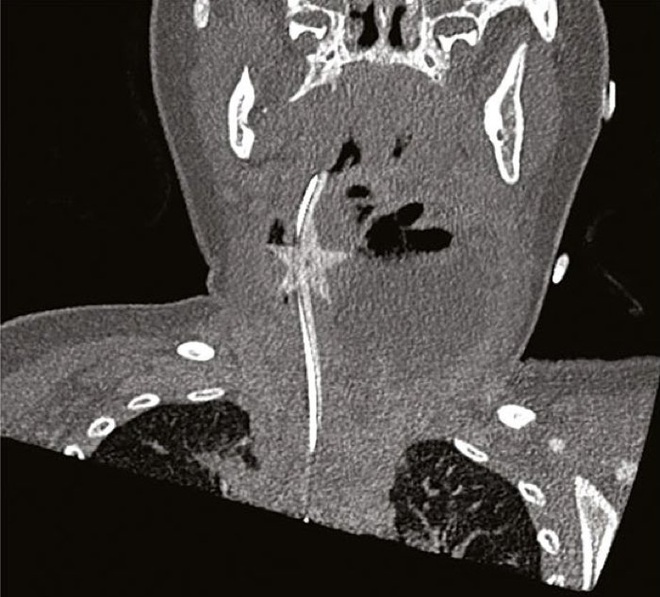

Ảnh chụp siêu âm và phim cắt lớp CT cho thấy có một khối mủ lớn (thuật ngữ y khoa gọi là áp xe) phía sau cổ họng của bé, chính khối áp xe này đã làm chặn đường thở khiến bệnh nhân thở nặng - và nó không chỉ đứng đó một mình.

Ảnh CT tái tạo đã tiết lộ thủ phạm cuối cùng đã gây ra tất cả các triệu chứng ngay từ ngày đầu, đó là một vật thể hình ngôi sao ẩn nấp bên trong khối mủ áp xe, một ngôi sao trang trí Noel đã dính chặt vào lớp mô mỏng trong khí quản của bé.

Ảnh CT tái tạo đã cho thấy có một ngôi sao trang trí Noel đã dính chặt vào lớp mô mỏng trong khí quản của bé.